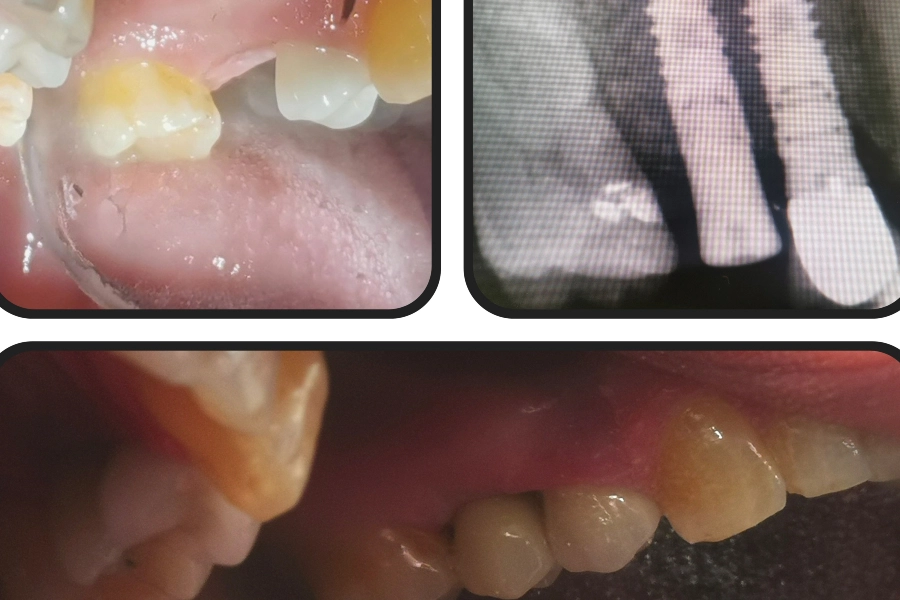

Ο Ξενέλλης Άρης είναι Χειρουργός Οδοντίατρος με ιδιωτικό οδοντιατρείο στο Παλαιό Φάληρο. Είναι απόφοιτος της Οδοντιατρικής Σχολής του Εθνικού και Καποδιστριακού Πανεπιστημίου Αθηνών. Μετά την ολοκλήρωση των σπουδών του, μετεκπαιδεύτηκε στα "Οδοντικά Εμφυτεύματα" στην Εταιρεία Οδοντοστοματολογικής Ερεύνης (ΕΟΕ), σε συνεργασία με την German Society of Oral Implantology (DGOI). Κατά τη διάρκεια της επαγγελματικής του πορείας, υπήρξε Βοηθός Γναθοχειρουργικής στο Γενικό Νοσοκομείο Αθηνών "Ιπποκράτειο" και στο Γενικό Νοσοκομείο Αθηνών "Ο Ευαγγελισμός", ενώ έχει εργαστεί ως Χειρουργός Οδοντίατρος στο 401 Γενικό Στρατιωτικό Νοσοκομείο Αθηνών, αποκομίζοντας πλούσια κλινική εμπειρία. Αξίζει να σημειωθεί πως, είναι πιστοποιημένος στην τεχνική της οστεοσυμπύκνωσης, μια καινοτόμα μέθοδο που εφαρμόζεται στα οδοντικά εμφυτεύματα. Επιπλέον, διατελεί μέλος του Οδοντιατρικού Συλλόγου Αττικής (Ο.Σ.Α.). Στο άρτια εξοπλισμένο οδοντιατρείο του, δίνοντας ιδιαίτερη έμφαση στις ανάγκες και στις ανησυχίες του κάθε ασθενούς, προσφέρει ένα ευρύ φάσμα υπηρεσιών γενικής, προληπτικής και αισθητικής οδοντιατρικής, όπως χειρουργική στόματος και τοποθέτηση εμφυτευμάτων.

Ανασύσταση δοντιού με άξονα

- 140€

Χειρουργική εξαγωγή έγκλειστων - ημιέγκλειστων δοντιών

120€

- 150€